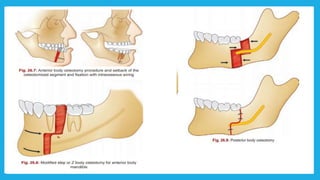

Mandibular orthognathic surgery Itcan be divided into several section:-  Surgery in which the jaw is moved in antrio-posterior direction by an osteotomy either in the ramus or body of the mandible  Surgery to the dentoalveolar area, such as segmental surgery to shift the teeth and alveolus but maintaining the integrity of the lower part of the mandible  Surgery into the chin, moving it in superior , inferior , posterior or anterior direction sometimes accompanied by reshaping

Mandibular segmental procedures Anterior subapical procedure